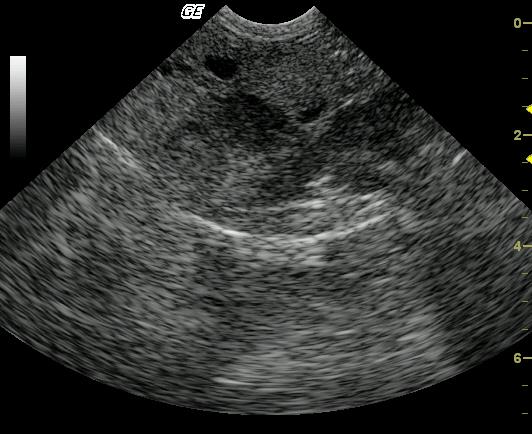

A 9-year-old FS DLH cat was presented with anorexia. Physical examination revealed mild dehydration and poor body condition. Mildly elevated SAP and mildly elevated ALT were found in the blood chemistry profile. Urinalysis was unremarkable.